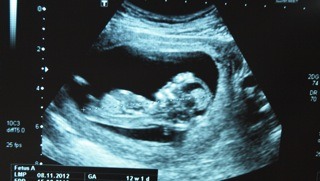

Hey guys... Here's the only shot I have of the nub. It's rather forked in the negatives I have, and this was the best I could do to get a pic of it. :)

I'm 12 weeks according to my dates but bub is measuring 12w 6d.

Leaning boy.

Slight boy lean but the spine is a little curled

Slight boy lean.

I'd say boy based on the angle - I'm not pro though so don't trust my opinion! Congrats on a healthy babe! xx

I would lean boy based n angle Cause it's def not parallel to the spine... Are you able to get any of the negs up? I think there is still hope for this to be a girl

The spine does seem to have a slight curl, so that may distort the upwards angle? I am not an expert. I know your wanting pink, so I have my fingers crossed for you.

Im sitting on the fence with this one - hoping its a pink bundle for you :) Measuring 12+6 I would have thought it would be angled more??